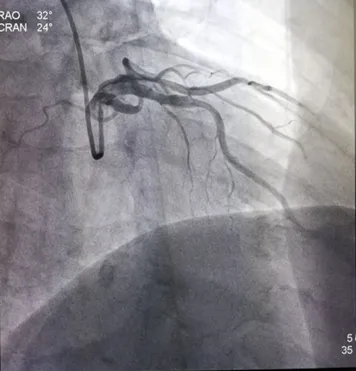

冠脉造影:入院第8天

右肩位:LAD近段约50%狭窄,中段约50%狭窄。

造影结果:冠脉多支病变,LAD近、中段50%狭窄,LCX 中段75%狭窄,D2 近段70%狭窄RCA近段50%狭窄,PDA近段60%狭窄。

患者多支血管病变,行FFR检查LCX :0.78,D2:0.77治疗策略:暂可以不行PCI治疗,继续纠正心衰治疗。